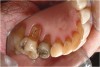

Characteristics of damage to tooth structures caused by acidity include wear on the occlusal surfaces of molars and a saucer shape on the cusps of molars (perimolysis).12 The erosion can vary from minor and subtle changes on the tooth surface, ie, loss of luster, a dull or matted look, to cupping on occlusal surfaces or incisal edges, which may extend to dentin. Usually, the erosive lesions demonstrate greater width than depth. When combined with abrasive forces or stresses, the tooth surface loss may occur at a faster rate (Figure 2, Figure 3, Figure 4 and Figure 5).

Figure  3  Severe dental erosion and attrition in a GERD patient.

Figure 3